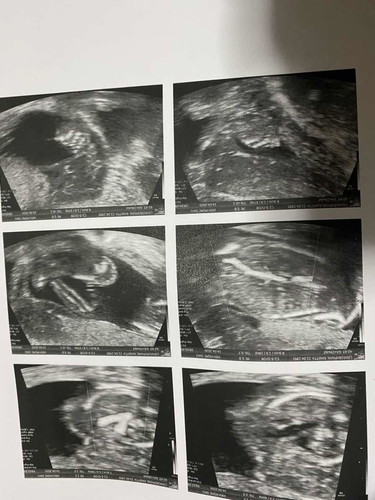

น้องเพศอะไรคะ

อยากรู้ดูเพศภาพไหนคะ...

น่าจะ 👧 นะคะ ในภาพที่ 2 ล่างสุด ซ้ายมือ เหมือนน้องกางขา เแล้วเห็นขีดๆ ออกตัวก่อนนะคะว่าไม่แน่ใจ และดูไม่เก่ง 😅